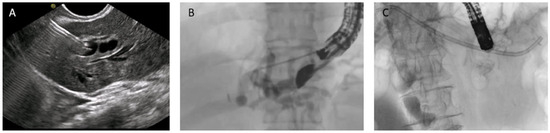

Figure 8. EUS-guided hepaticogastrostomy (HGS). (A) Puncture of the intrahepatic duct, EUS view; (B) puncture of the intrahepatic duct, radiologic image; (C) placement of a plastic stent to ensure biliary drainage.

HGS has become a crucial therapeutic option in cases where conventional ERCP fails or is contraindicated, particularly in patients with SAA, malignant duodenal obstruction, or inaccessible ampulla. HGS creates a permanent fistula between the intrahepatic ducts (typically segment II or III) and the gastric lumen, using a hybrid SEMS specifically designed for EUS-guided HGS. It is a partially covered hybrid stent with two functional segments: the intrahepatic portion is uncovered, allowing anchorage within the liver parenchyma, while the gastric portion is fully covered and equipped with an anti-migration flange, minimizing the risk of bile leakage and stent dislodgement [38]. Before the advent of dedicated hybrid stents, and in centers where these devices are not available, plastic stents have been used (Figure 8); in this setting, a long stent is suggested to avoid dislodgement [46]. Technical aspects include careful puncture to avoid vascular structures, gentle dilation of the tract, and deployment of covered SEMS to minimize bile leak.